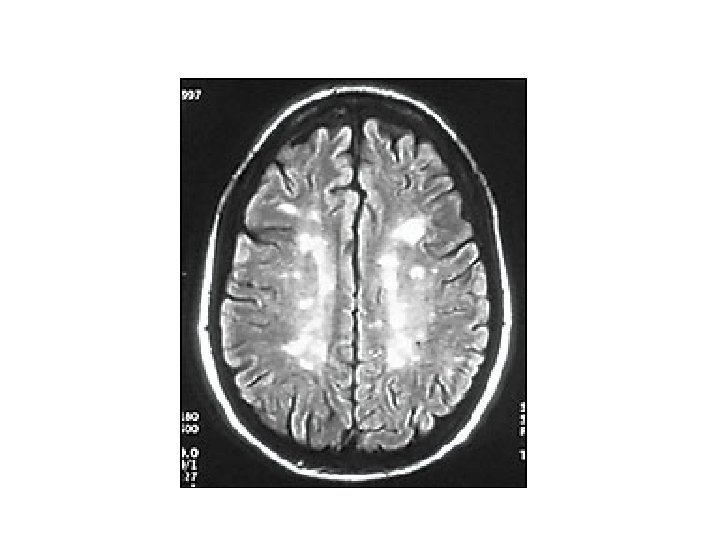

MRI BULGULARI • Periventriküler ak maddede plaklar • Serebellum / beyinsapı / servikal ve torakal spinal kord • Kontrast madde (Gadolinium) tutulumu aktif lezyon varlığını gösterir – Her zaman hastalık aktivitesinde artış ile korelasyon göstermez

MRI • MRI anormalliği: – Kesin MS’de %90 – Olası MS’de % 70

AK MADDE LEZYONLARI